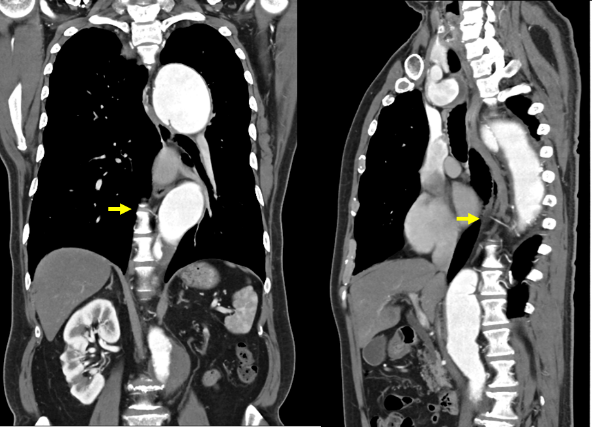

大動脈解離が原因の場合、動脈瘤が広範囲にわたることが多く脊髄を栄養する肋間動脈や腸・肝臓・膵臓や腎臓を栄養する腹部の動脈をどのように温存するかが重要になります。とくに脊髄の合併症が重篤であり、脊髄梗塞を発症すると下半身不随(対麻痺)や直腸膀胱障害を起こします。脊髄梗塞を予防する方法がこれまでに多数報告されてきておりますが、当院では術前の脊髄動脈(Adamkiewics動脈)の特定(CT、MRI)を行っております。脊髄動脈は、肋間動脈の第7肋間動脈~第4腰動脈のいずれかから栄養されているといわれています。これまでは同定が困難といわれていましたが、臨床画像の進化により最近ではある程度同定ができるようになってきました。脊髄動脈の特定を予め行っておくことで重要な肋間動脈を選択に再建することが可能になり、これにより対麻痺の発症を下げることができるようになりました。また脊髄梗梗塞の危険性が高い方には、脊髄ドレナージ(術前・術後に脊髄腔へ管を入れる)を行うことで、ある程度予防また治療を行うことができます。

CTやMRIによる脊髄動脈の特定が困難な場合、患者様の状態によって肋間動脈をまとめて再建する方法を当科では行っております。これがVascular

Tube Technique(血管ロール法)による肋間動脈再建法です。この方法のメリットは、脊髄動脈を同定する必要がなくたくさんの肋間動脈を一気に再建できる点にあります。これにより脊髄動脈虚血を防ぎ、その虚血時間も短時間にできること、出血リスクをさげることができます。当院では、2004年頃よりVascular